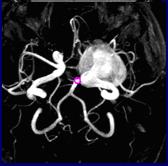

A felbontóképessége a módszer olyan magas, hogy lehetővé válik, hogy megkapjuk kijelző fő hajók - artériák és vénák (angiográfia), még akkor is anélkül, hogy a kontrasztanyagok alkalmazása. Az alkalmazás módja A mágneses rezonancia angiográfiát elkerüli fenyegető betegségek, mint például aneurizma és arteriovenosus fejlődési.

Beteg K. 46 év. A mágneses rezonancia angiográfiát (referencia nélkül kontrasztanyag) feltárta egy óriás aneurizma a baloldali belső nyaki artériába. Küldtem egyeztetési érrendszeri idegsebész.